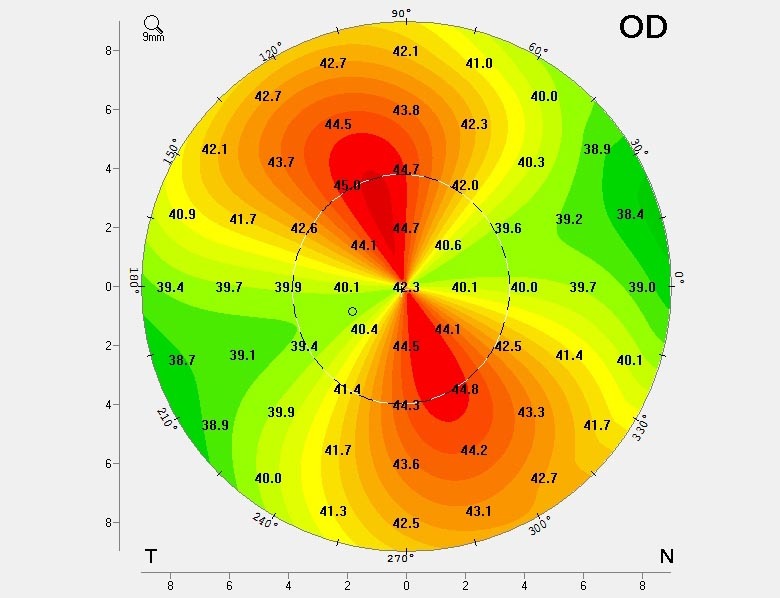

Die Hornhaut ist in eine Richtung stärker gekrümmt als in die andere. Dreidimensional sieht die Hornhaut aus wie ein Ei. Diese Form verzerrt die Sicht, kann aber mit einer Brille problemlos korrigiert werden, da die Verzerrung symmetrisch ist.

Diese Hornhaut ist erkrankt und benötigt weitere Untersuchungen/Behandlungen. Man erkennt, dass die Hornhaut im oberen Anteil flach ist und im unteren Anteil sehr stark vorgewölbt. Die Sehkraft ist verzerrt, es bestehen Doppel- oder sogar Dreifach- und Vierfach-Bilder und in vielen Fällen kann auch eine Brille die Sehschärfe nicht mehr wiederherstellen. Zudem ist die Krankheit fortschreitend und kann vor allem bei Kindern und Jugendlichen bis zu schwersten Sehbehinderungen führen.